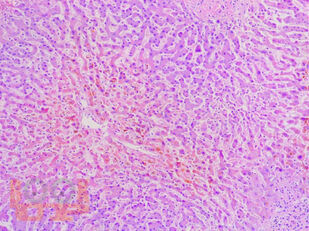

В учебном пособии представлен теоретический материал, перечень макропрепаратов и микропрепаратов, демонстрирующих типовые проявления патологических процессов. В цветных иллюстрациях и в описании микропрепаратов сделан акцент на наиболее важных гистологических изменениях, позволяющих на светооптическом уровне диагностировать и дифференцировать состояния, отклоняющиеся от нормы, в том числе с использованием различных гистологических окрасок. Пособие помогает выделить главные аспекты изучаемых патологических процессов, организовать и конкретизировать учебный процесс.